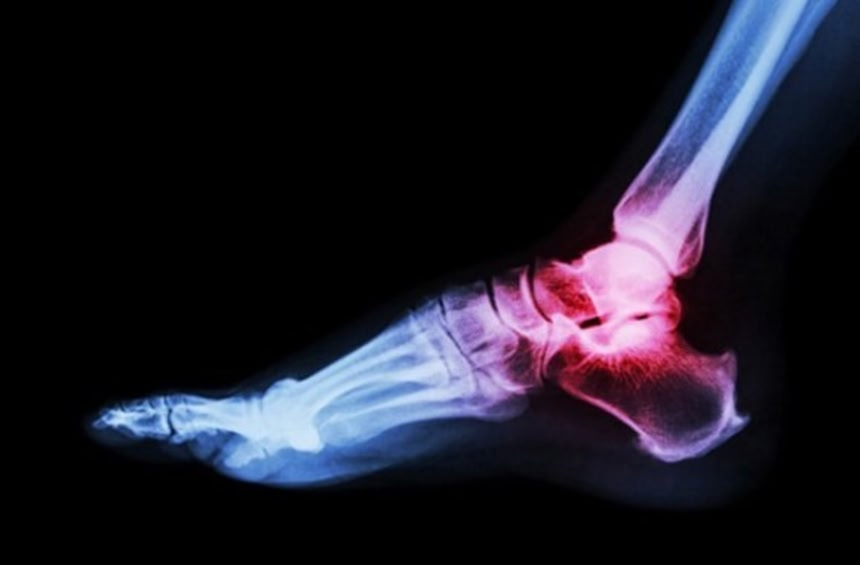

10. 折れない骨

この画像を大きなサイズで見る骨折したら数か月が台無しになる。骨は人体で最も硬い物質でありながら、案外よく折れる。が、LRP5という遺伝子の突然変異があれば心配無用だ。

LRP5は骨密度に関連する。これまで、この遺伝子の突然変異が骨粗鬆症を引き起こすことは知られていた。しかし最近になって反対の効果を生むことも判明した。アメリカに住むある家族はLRP5に突然変異があるが、ほとんど折れないくらいに骨密度が高いのである。脊椎、頭蓋骨、骨盤まで、この一家は地球上で最強の骸骨を持っている。

専門家によると、この突然変異が骨の成長シグナルを出しすぎるのだという。将来的に骨に関連する疾病の治療に応用される日が来るかもしれない。